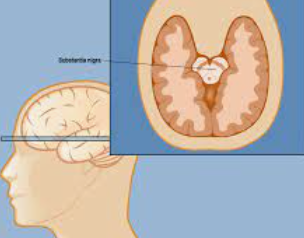

파킨슨병은 운동 조절에 관여하는 뇌의 일부인 흑색질에서 도파민 생성 세포의 점진적인 퇴화로 인해 발생하는 운동 장애 증상입니다. 유전적 요인과 환경적 요인이 복합적으로 작용하는 것으로 널리 알려져 있지만 이 퇴행의 원인은 거의 알려지지 않았습니다.